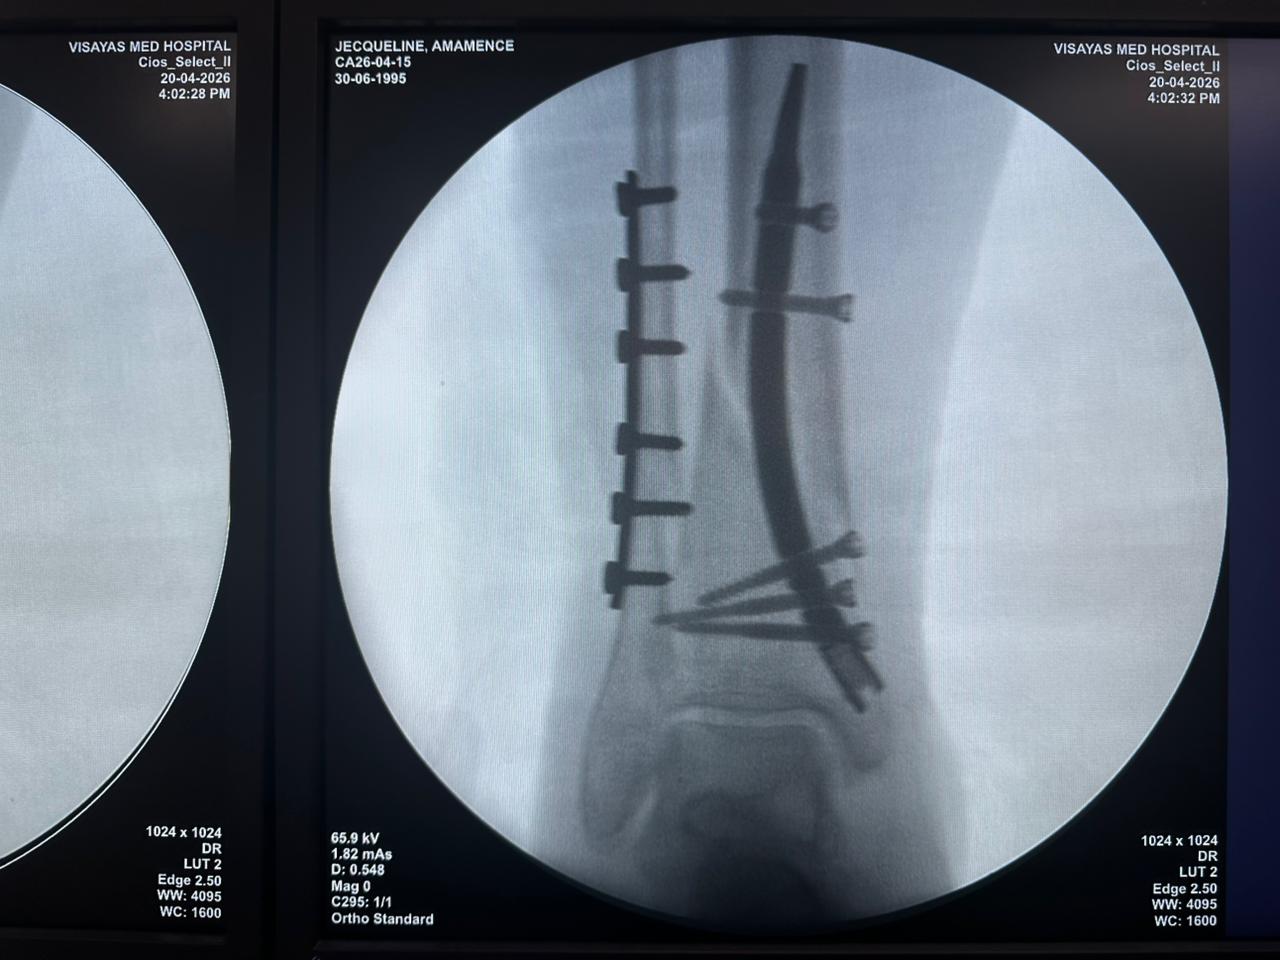

Caso di studio sulla fissazione del chiodo tibiale distale con supporto per placca peroneale

Fluoroscopia intraoperatoria con arco a C, viste AP e laterali

Questo caso prevedeva la fissazione tibiale distale utilizzando un chiodo tibiale distale intramidollare. La fluoroscopia intraoperatoria ha confermato la posizione del chiodo, delle viti di bloccaggio distali e della fissazione della placca peroneale.